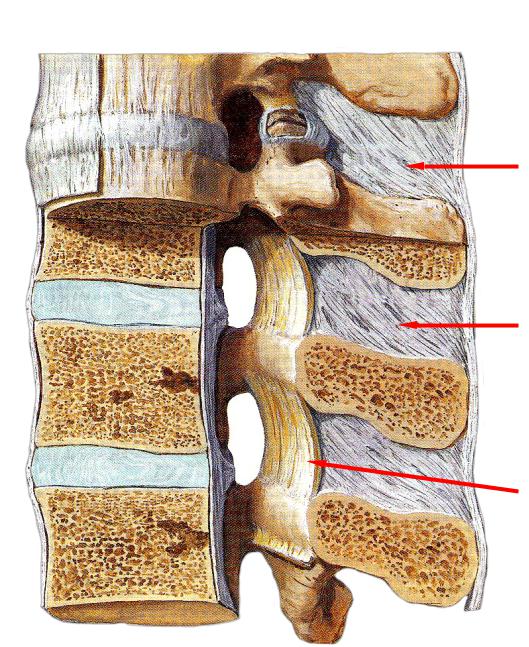

Структура и анатомия синдесмоза: научные иллюстрации